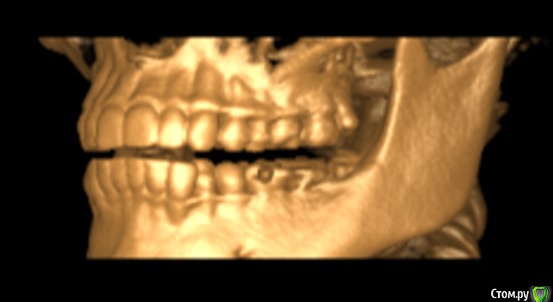

Мне 25 лет. Три месяца назад на НЧ начал расти восьмой зуб с левой стороны. Все проходило без осложнений. Но примерно две недели назад я заметила, что 3 и 4 зубы с той строны начали кривиться. До этого жалоб на прикус никогда не было, зубы были нормальные.

Паралельно с этим два месяца назад было начато лечение 7ого зуба с той же стороны.  Зуб с проблемными каналами в которых, как обнаружилось в ходе лечения, предыдущий врач оставил зацементированый инструмент.  Когда я сообщила доктору о проблеме с искривлением, был назначен прием с присутствием ортодонта.

К сожалению снимков до искривления нет. Но есть свежая 3D комп.томография I-CAT.  Приложу любые нужные ракурсы.